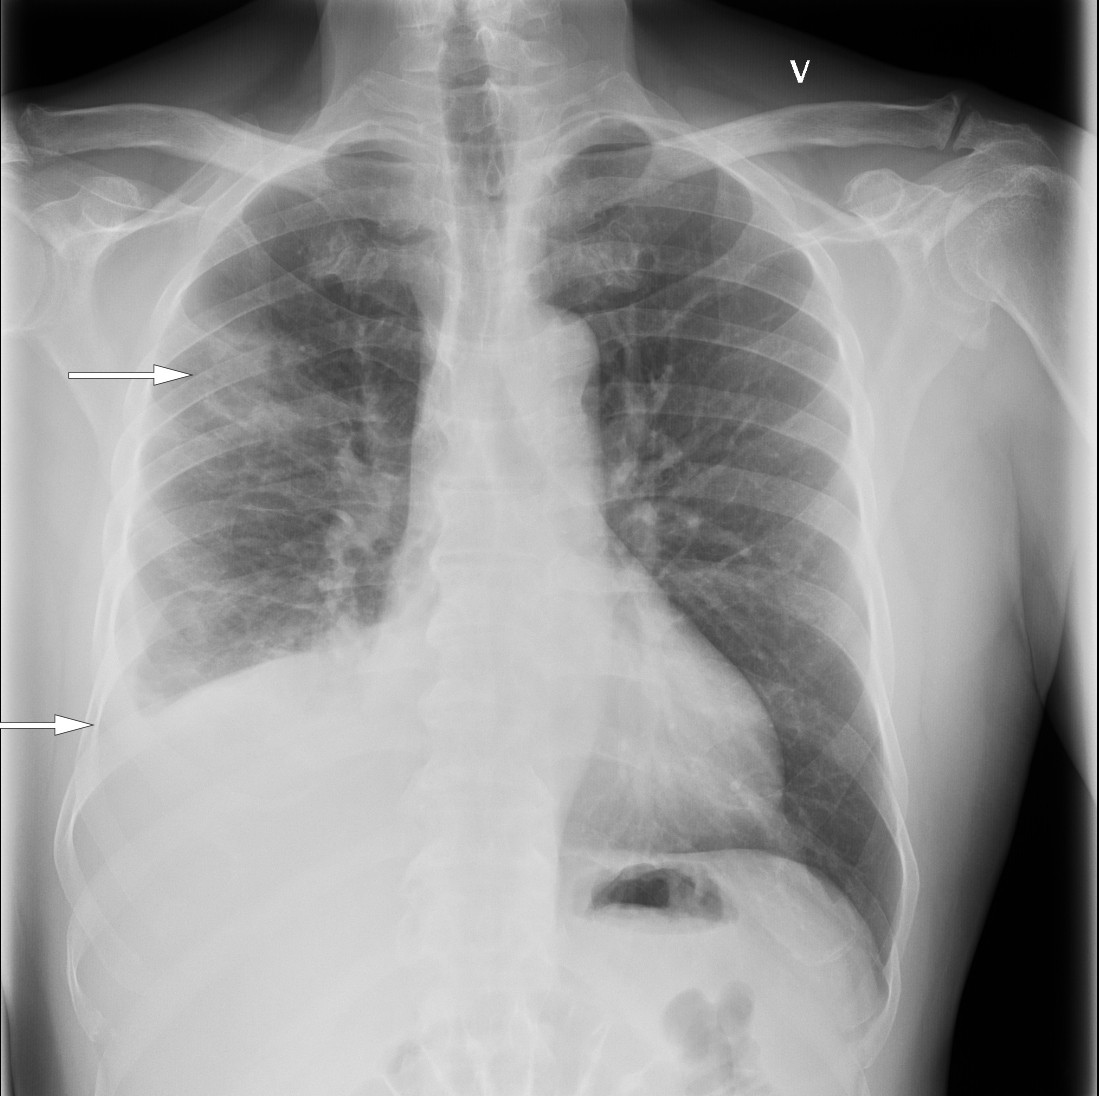

På sykehuset var allmenntilstanden god. Blodtrykket var 168/84 mm Hg, puls 85 slag per minutt, temperatur 37,8 °C i øret, perifer oksygenmetning 97 % i romluft og respirasjonsfrekvens 20 per minutt. Han hadde en systolisk bilyd grad 1 over hjertet, best hørbar i andre høyre interkostalrom, og basalt over høyre lunge var det svekket respirasjonslyd med perkutatorisk dempning. Han hadde ingen cyanose, lymfeknutesvulst, fortykkelse av fingre og tær (clubbing), urglassnegler, palpabel hepatosplenomegali, eksantemer eller perifere ødemer. Blodprøvene viste CRP 105 mg/L og albumin 34,4 g/L (35–45 g/L). Hematologiske prøver, elektrolytter, nyre-, lever- og galleprøver var alle innenfor normale grenser. Røntgen thorax (figur 1) viste flere delvis konsoliderte fortetninger, særlig i nedre del av høyre lunges overlapp, atelektasestriper og høyresidig pleuravæske. Mengden var for liten for drenasje. Basert på sykehistorien med tørrhoste, pneumonisuspekte fortetninger på lungerøntgen og moderat forhøyet CRP uten leukocytose, ble tilstanden oppfattet som en atypisk pneumoni. Pasienten ble utskrevet etter ett døgn med azitromycintabletter 500 mg daglig i tre dager. Azitromycin ble valgt til fordel for erytromycin på grunn av økt intracellulær konsentrasjon, økt sannsynlighet for etterlevelse og erfaringsmessig mindre sannsynlighet for gastrointestinale bivirkninger.

Ni uker etter første utskrivning ble han igjen innlagt på sykehuset av fastlegen. Han var tynn og avmagret og hadde i løpet av den aktuelle sykdomsperioden på over to måneder (figur 2) hatt et ufrivillig vekttap fra 75 kg til 62 kg. Den kliniske undersøkelsen ved innkomst var ellers identisk som ved forrige innleggelse. Mens fortetningene på røntgenbildet tatt ni uker tidligere var uendret, var mengden pleuravæske økt og nå tilgjengelig for tapping. Pasienten var anemisk, med hemoglobin 12,4 g/dl (13,2–16,5 g/dL), albuminverdien var redusert til 29,8 g/L, CRP var 152 mg/L og leukocyttallet normalt. Hivtest og blodkulturer var negative.